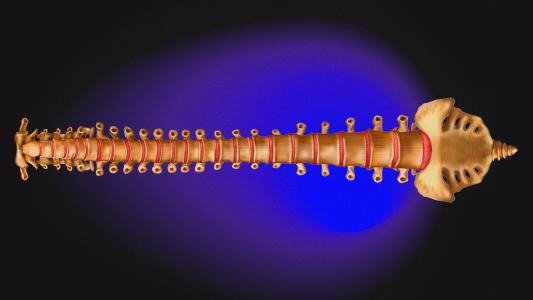

Spinal cord implants help paralyzed people walk again

A new spinal cord implant uses electricity to reawaken spinal neurons.